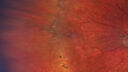

15 year old boy with Loeys-Deitz Syndrome. And TGFBR gene positivity. At age 11 he had aortic root surgery. VA 20/25 OU. Anterior segment normal. Retina shows findings consistent with mild familial exudative vitreoretinopathy